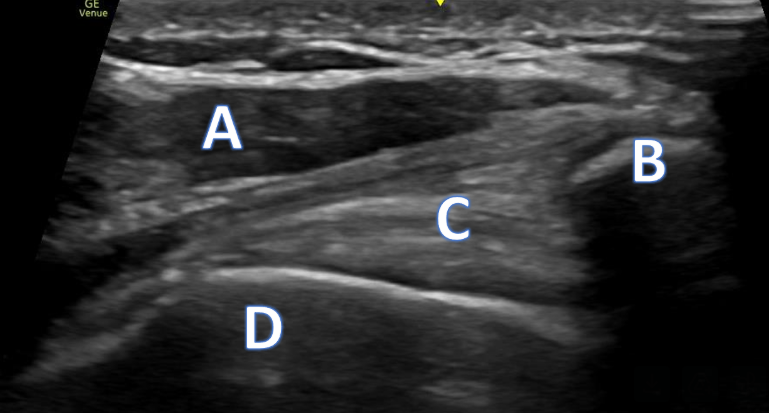

A 21-year-old female presents to the emergency room after falling from dancing on a table and injuring her right ankle. She is in severe pain and unable to bear weight comfortably with swelling and tenderness along the lateral malleolus. X-rays are taken and shown above.